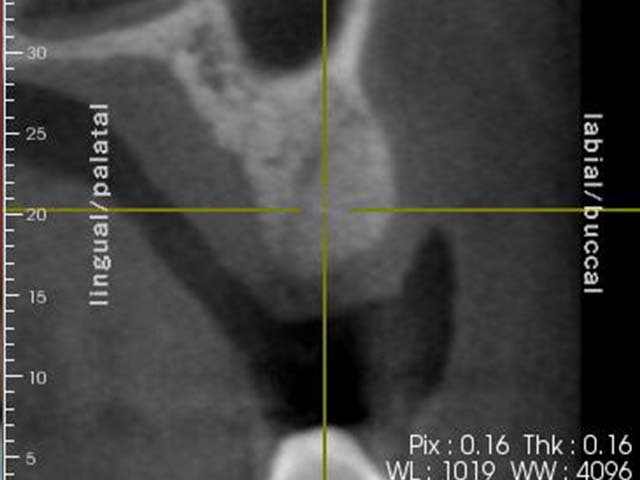

齒槽骨保存術+植牙 首頁 案例分享 人工植牙 齒槽骨保存術+植牙 STEP1拔除掉無法使用的斷裂牙根 STEP2齒槽骨保存術—使用骨粉填補拔牙傷口 術前 V.S 術後 植牙第一階段—植入牙根 植牙第二階段—製作正式假牙